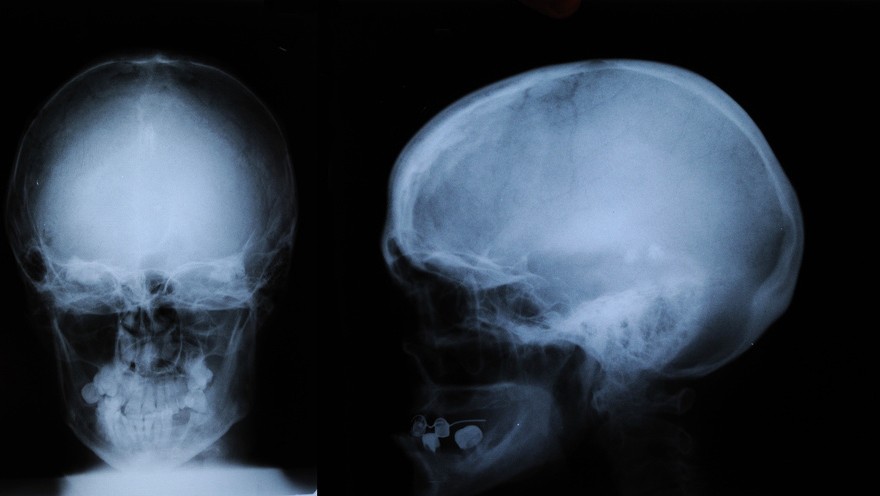

Анатомия мозга: Рентгеновские снимки для презентаций